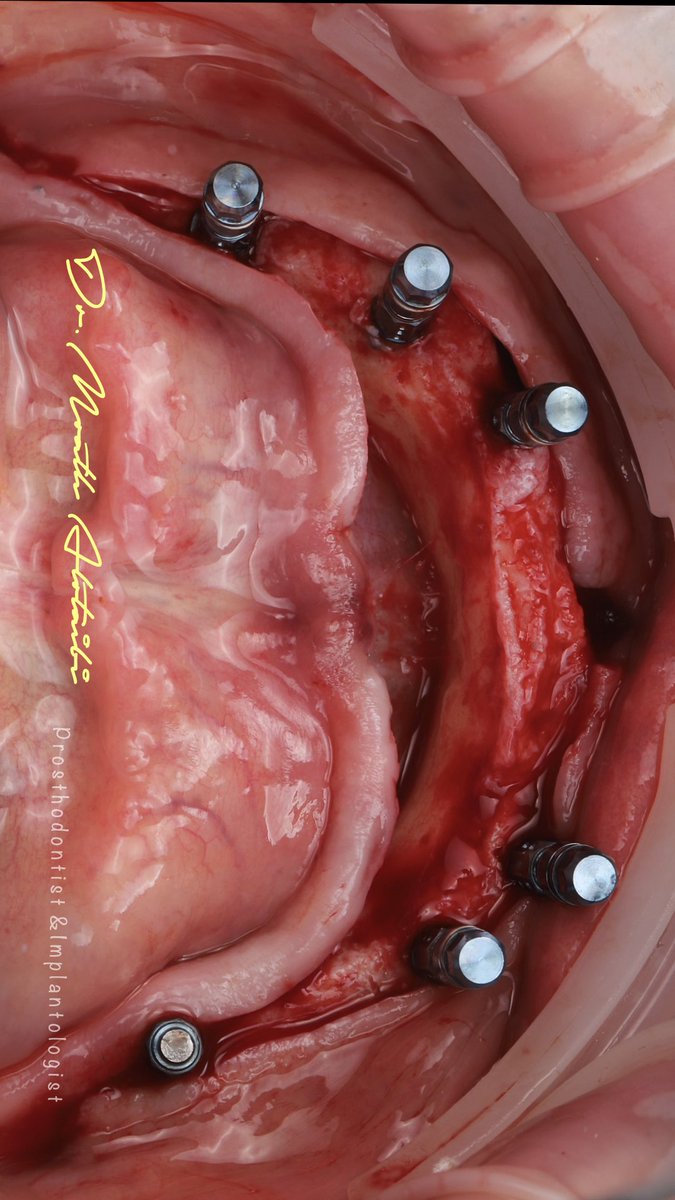

حالة إعادة تأهيل كامل للفكين لمراجعي عن طريق زراعة العظم والاسنان والتركيبات.. الجزء الجراحي مع المعماري الكبير د.ياسر د.ياسر الزهراني 😍 وكل الشكر للمراجع على تحمله خطتي العلاجيه ورحلة العلاج المطوّلة🌹